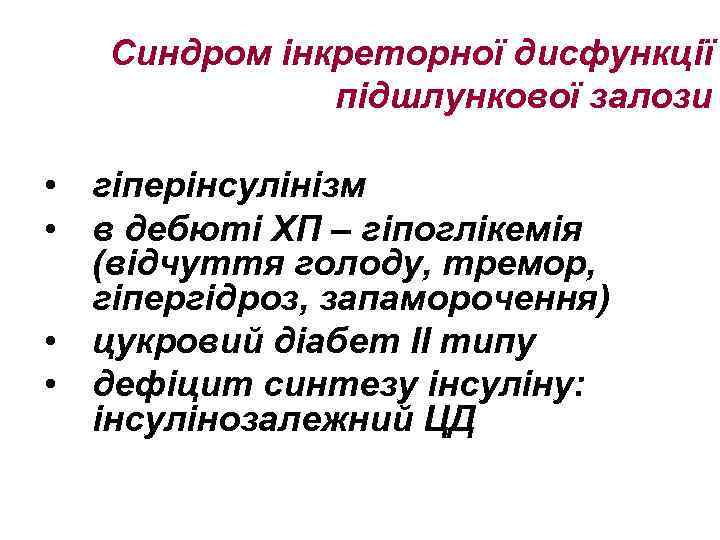

Синдром інкреторної дисфункції підшлункової залози • гіперінсулінізм • в дебюті ХП – гіпоглікемія (відчуття голоду, тремор, гіпергідроз, запаморочення) • цукровий діабет ІІ типу • дефіцит синтезу інсуліну: інсулінозалежний ЦД

Синдром інкреторної дисфункції підшлункової залози • гіперінсулінізм • в дебюті ХП – гіпоглікемія (відчуття голоду, тремор, гіпергідроз, запаморочення) • цукровий діабет ІІ типу • дефіцит синтезу інсуліну: інсулінозалежний ЦД